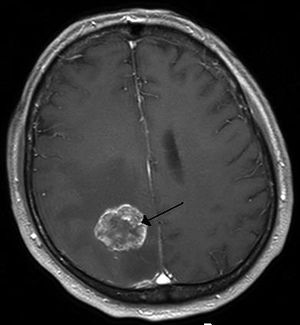

Brain metastasis in the right cerebral hemisphere from lung cancer shown on T1-weighted magnetic resonance imaging with intravenous contrast. (L=left, P=posterior, back of the head)